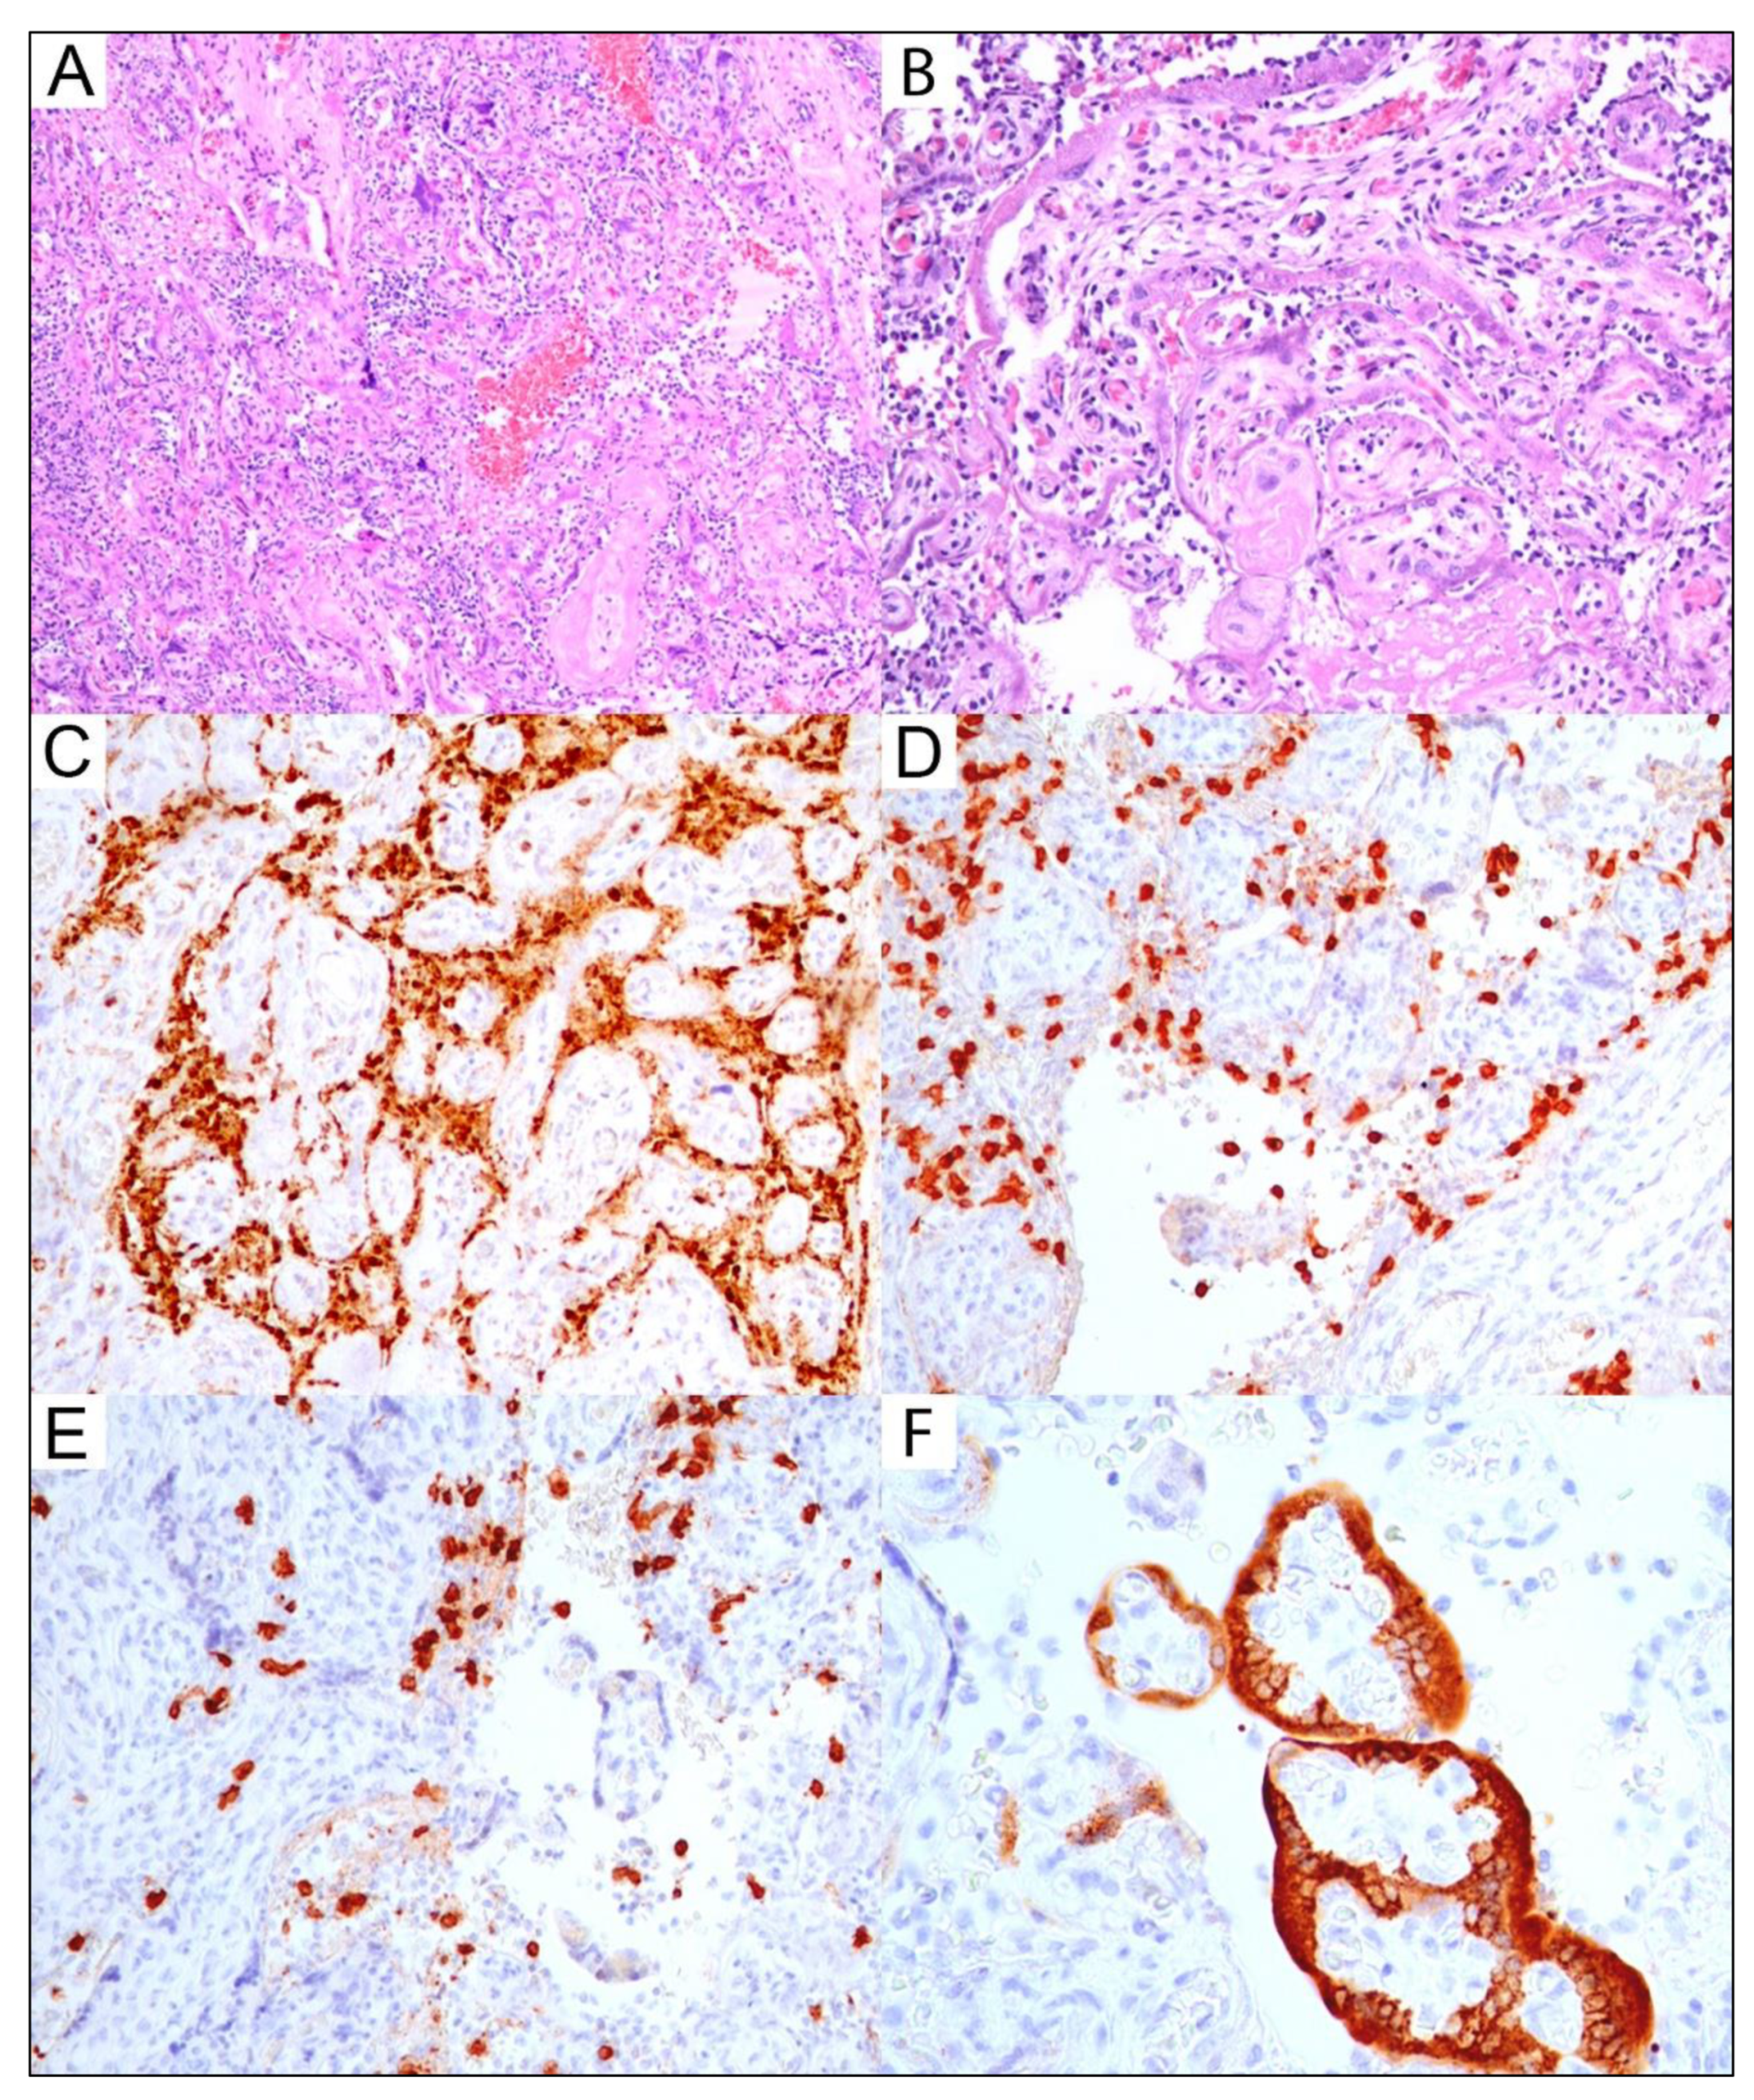

Figure 2. Severe pathological findings identified in a placenta with a positive SARS-CoV-2 immunoprofile from a SARS-CoV-2-positive mother. Neonate had a result positive result for a nasopharyngeal swab. Massive chronic intervillositis: (A): Intervillous space is massively involved by inflammatory infiltrate that significantly impairs fetal–maternal exchange and adversely affects fetal wellbeing; H&E-stained section at original magnification, 10×. (B): Destruction of the placental barrier is seen as early necrosis (loss of nuclear basophilia) of the villous trophoblast; H&E slide; original magnification, 20×. (C): The picture shows the predominant histiocytic component of the inflammatory infiltrate in the intervillous space; positive immunoexpression for CD68 antibody; original magnification, 20×. (D): The picture shows the CD3+ T-lymphocytes component of the inflammatory infiltrate in the intervillous space; positive immunoexpression for CD3 antibody; original magnification, 20×. (E): The picture shows the CD8+ T-lymphocytes component of the inflammatory infiltrate in the intervillous space; positive immunoexpression for CD8 antibody; original magnification, 40×. (F): SARS-CoV-2 placentitis: the picture shows strong positive and confluent immunoexpression in villous trophoblast for SARS-CoV-2 antibody. Placental viral infection triggered massive chronic intervillositis presented in (AE); original magnification 40×.